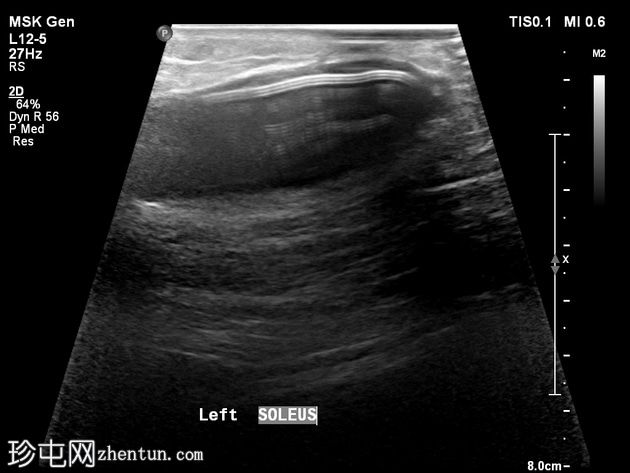

X线片

正位片

PACS系统回顾显示既往右膝关节平片。可见内侧小腿植入物,在膝关节X线片上部分显影。正位片上易于识别,但在侧位片上可能被忽略,尤其是在缺乏病史的情况下。